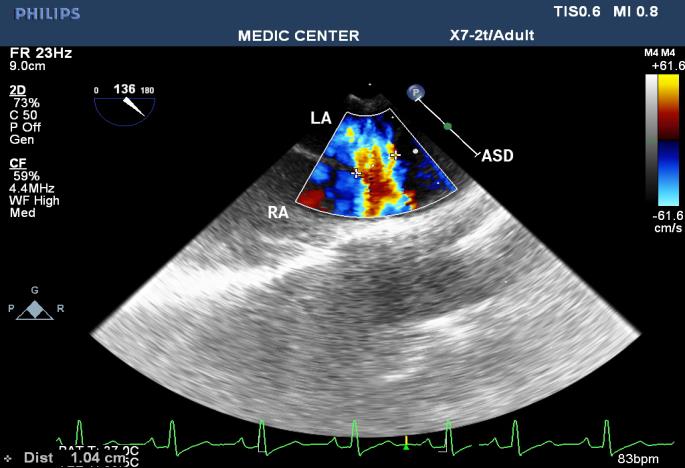

Among 204 Pts with ASD, The secundum defects account for approximately 78%, then primum ASDs 6%, sinus venosus ASDs 12%, multiple shunt ASD 4%, unroofed coronary sinus not seen. 3D TEE can assess the size of ASD and the circumferential rims to select Patients for Transcatether closure. Currently we perform ASD closure limited to ASDs less than 30mm and with at least 5mm of circumferential rims (Table 1).

The X-plan mode can be used to estimate the maximal diameter of defect in two orthogonal planes. Three-dimensional (3D) TEE imaging is an important adjunct to 2D imaging because multiplanar reconstruction ensures that the defect is measured accurately.

Three-dimensional (3D) TEE images can be rotated to demonstrate the defect from the RA or LA side in evaluating the secundum atrial septal defect rims. This improves understanding of their shape and relationships to surrounding intracardiac structures.

Multiple ASDs account only 4%, 3D TEE with wide sector can detect and visualize all the shunts through IAS (Figures 22-37).

Figure 26. L-R shunting secundum ASD demonstrated with color flow imaging